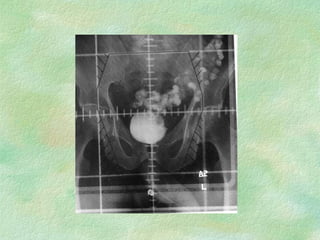

Conventional Simulation ImmobilizationDiagnostic energy X-rays replace Megavoltage beams Lower patient dose, better images, real-time fluoro External coordinate system same as treatment coordinate system

Volume Definition Externalreference palpation,visual radio-opaque markers Internal reference bony landmarks, other anatomical transfer from CT contrast agents, internal markers

Lateral Field Nodesoutlined With solder